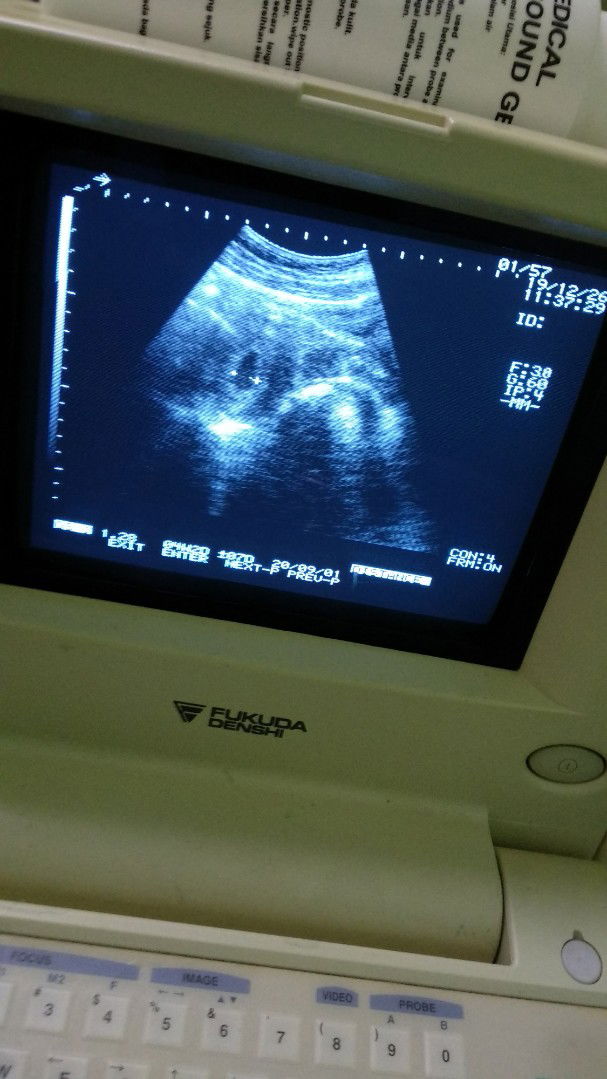

Lewat hpl dan ketuban sedikit keruh

Kemarin saya usg tepat 40 weeks (hpl) tapi baby tak kunjung lahir, di usg smua baik, ketuban cukup cuma ketuban sedikit keruh, dokter menyarankan saya utk induksi secepatnya krn tdk mau resiko, jujur saya sedikit galau krn tau mengenai minusnya induksi terutama ttg sakitnya, dilain sisi tidak mau jg menunggu lama2 tkt kenapa2 wlpn msh 40 weeks, yg sebenarnya msh bsa d tunggu cma y krn ketubann sedikit keruh saja, mnrt bunda bagaimana ya, ada apa ada yg punya pengalaman spt saya ketuban sedikit keruh